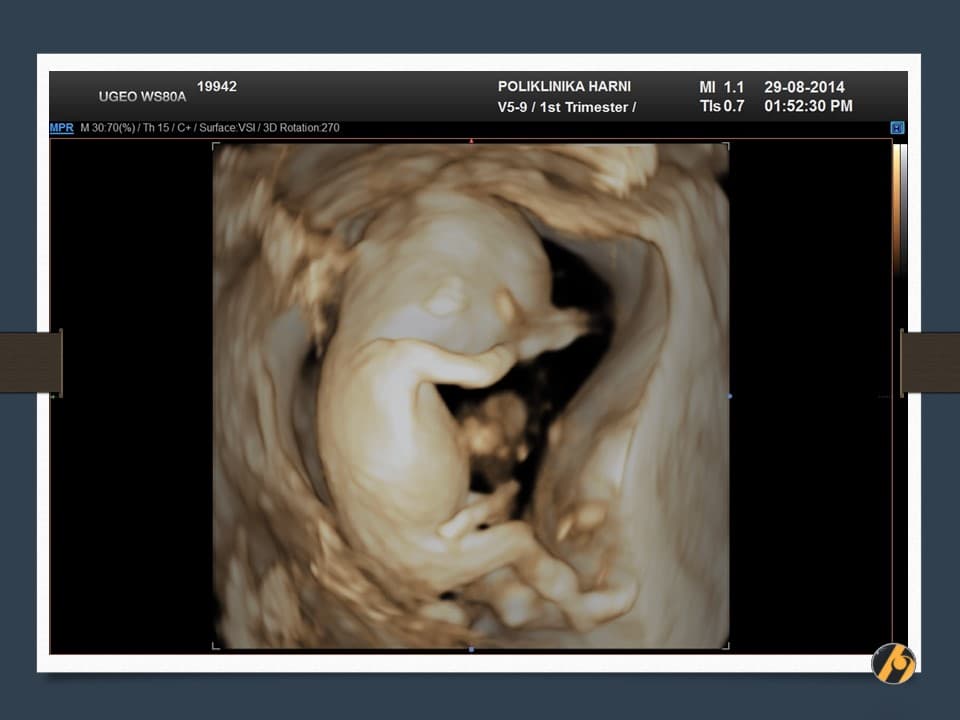

Konačno je dovršen veliki posao, završena je embriogeneza i vaša beba je kompletno razvijena. Od sada pa do konca trudnoće najveće promjene se odnose na dobitak na težini i rast bebe. Beba se od sada više ne naziva embrij, nego fetus.

Premda je dovršena embriogeneza, organogeneza i fetalni rast se nastavljaju ubrzanim tempom, pa je beba u zadnja dva tjedna udvostručila svoju težinu.

Nastavlja se oblikovanje lica koje je sve više nalik ljudskom licu. Razvitkom noktiju na rukama i nogama završava se razvitak prstića. Beba je veoma pokretna i kod ultrazvučnog pregleda se zapažaju nagli i snažni pokreti tipa trzaja - pokreti su spontanog karaktera, ali bez volje djeteta. U ovo vrijeme je kontrola pokreta djeteta još uvijek podređena živčanim središtima u leđnoj moždini, a moždani centri za koordinaciju pokreta još nisu razvijeni.

U ovome tjednu se crijeva u potpunosti smještaju u trbušnu šupljinu i ukoliko se prije vidjela omphalocoela (prisustvo crijeva u pupčanoj vrpci), sada se ta slika gubi. Formirano je i raspoznatljivo vanjsko spolovilo, koje se standardnim ultrazvučnim tehnikama još neko vrijeme neće moći raspoznati.

Vaša beba dugačka je oko 6.5 cm, a teška 10 - 15 g.